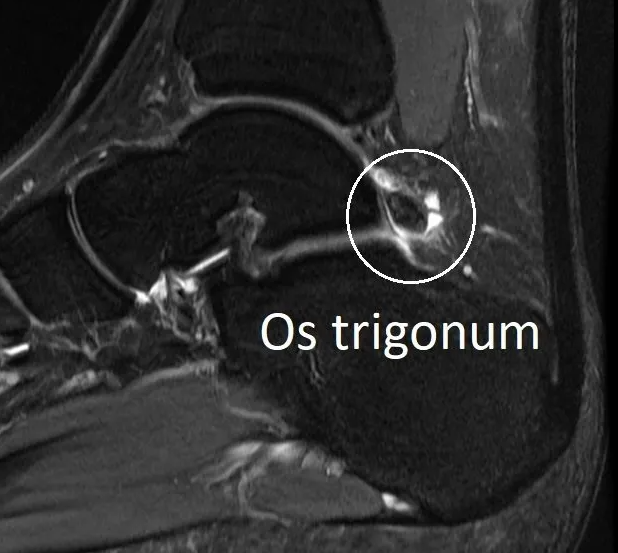

- 5% of people are born with an extra bone at the back of the ankle called an os trigonum. This makes posterior impingement more likely.

- investigations (X-ray, CT or MRI).

These investigations determine if the impingement is due to bone spurs, loose bone fragments, arthritis or just soft tissue scarring.